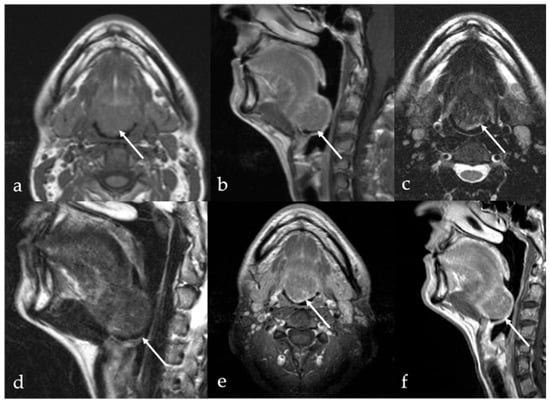

7.2. Ectopic Thyroid Tissue

| Thyroglossal duct cyst [15] Ectopic thyroid tissue [16] | Cyst Same features as thyroid tissue | Lingual tonsil mucous retention cyst Squamous cell carcinoma and lymphoma of the tongue base |